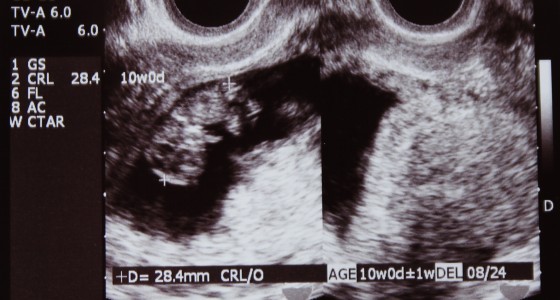

胎盤がまだ未完成なので子宮に何らかの傷で出血が起こっているとのこと。

幸い、ちびたんは無事だった。